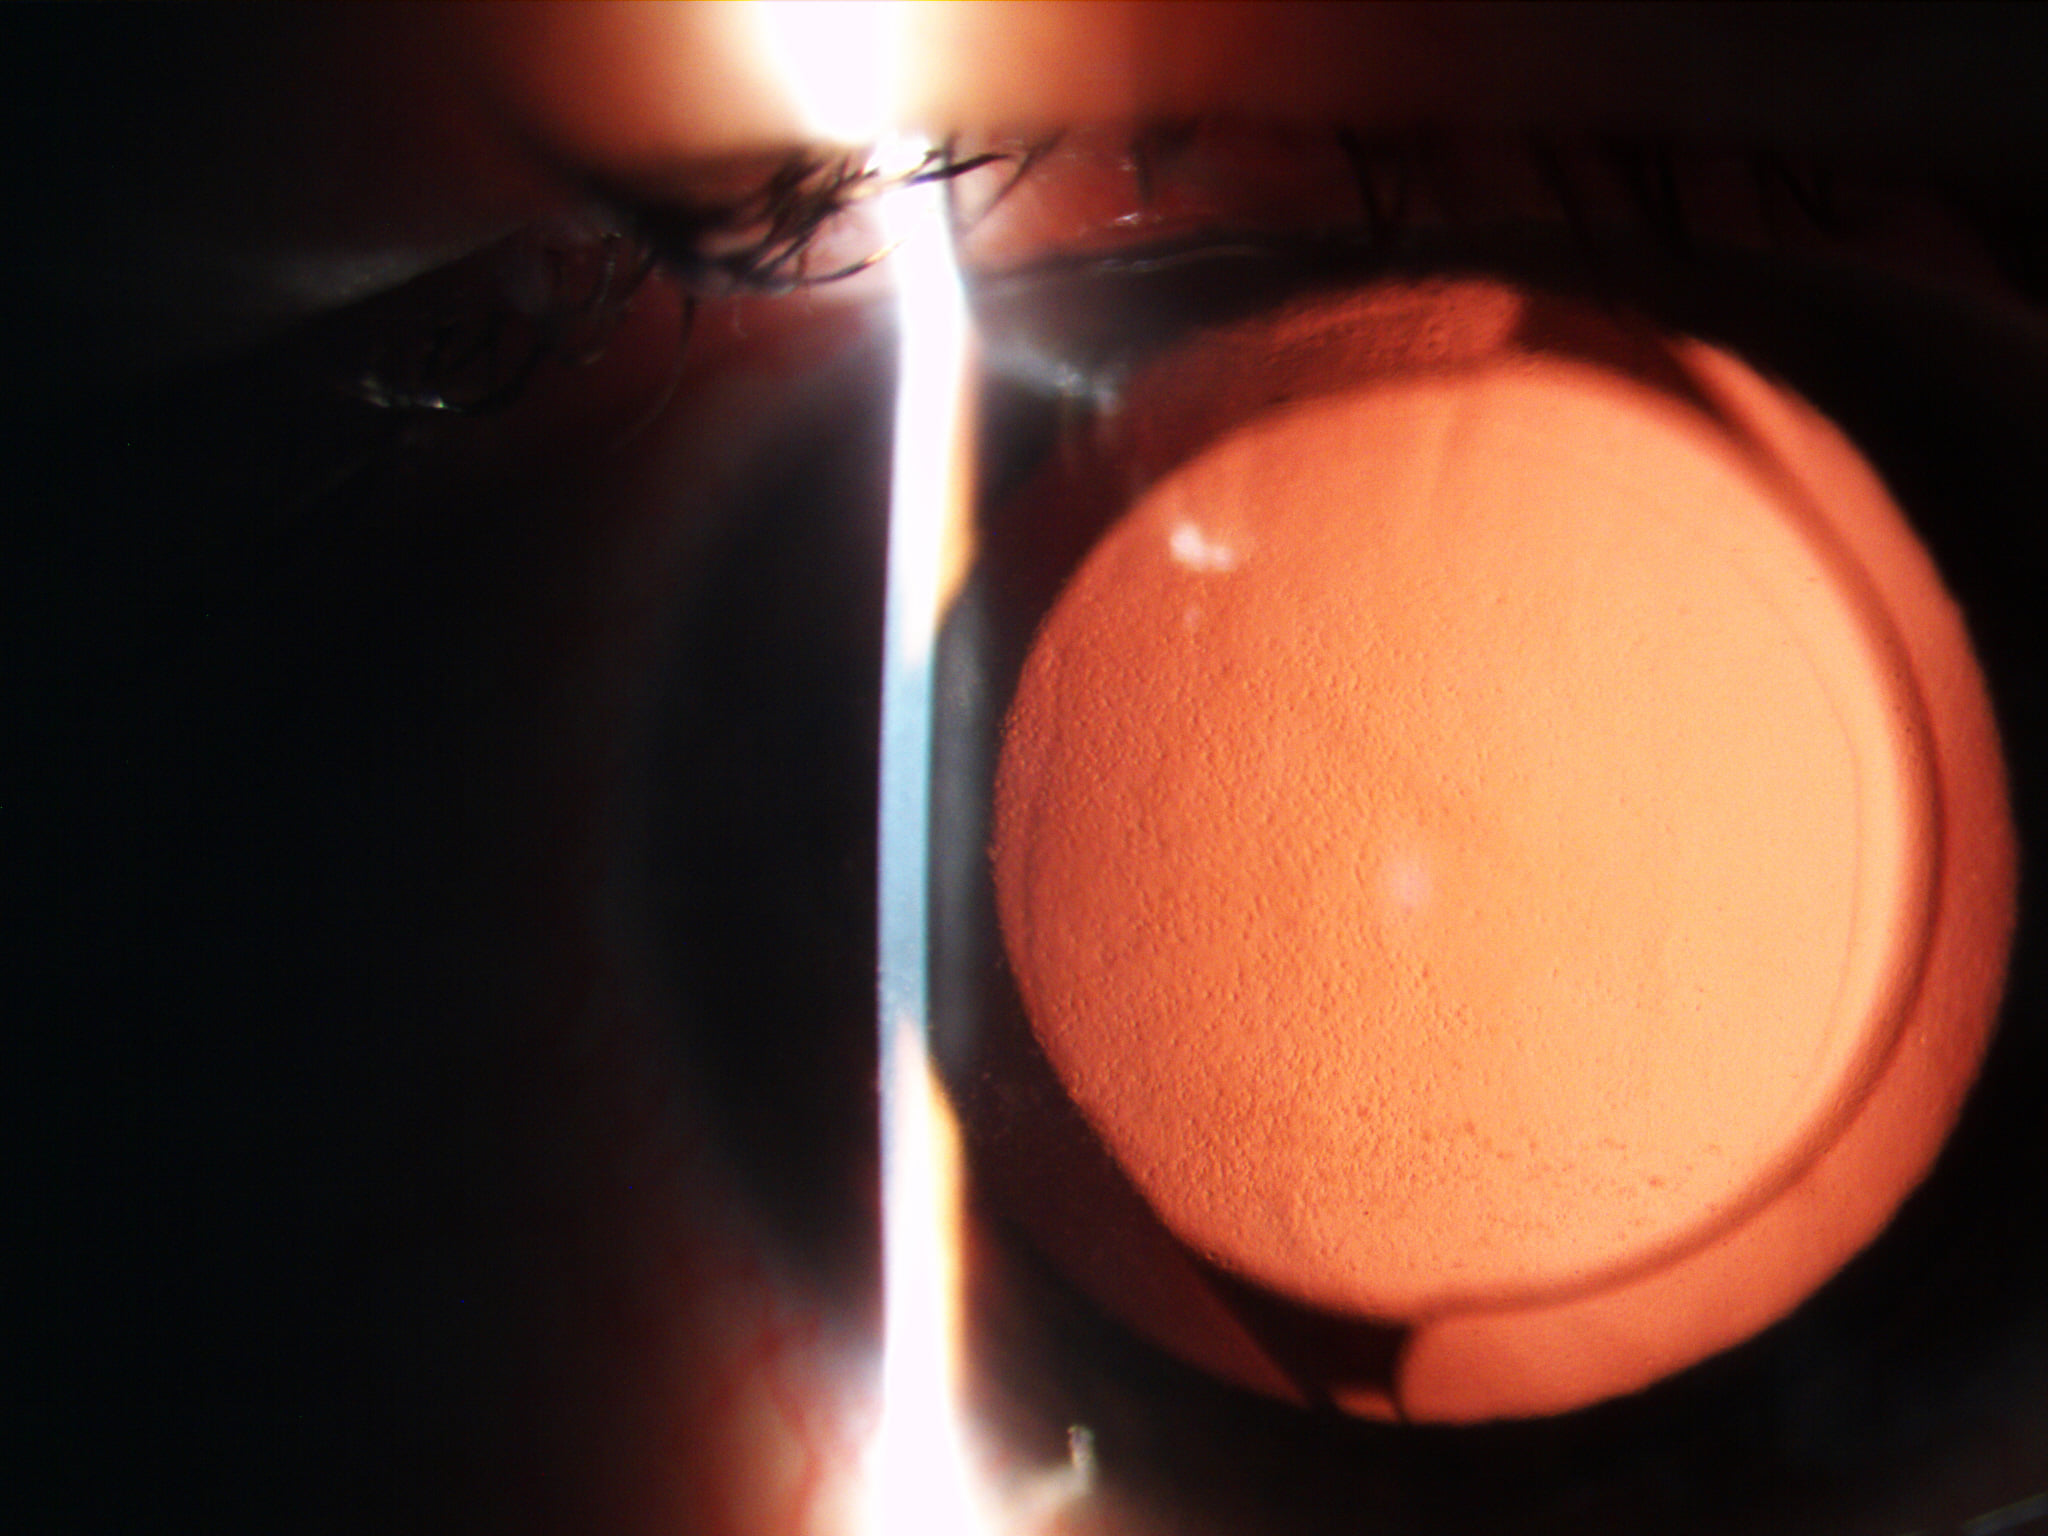

Mai jos, fotografii ale mai multor pacienti de-ai nostri cu Corneea Guttatta în faze medii, sau chiar avansate, la care am efectuat doar operația de cataractă, în urma căreia corneea a „supraviețuit” cu brio și nu a mai fost nevoie – cel puțin până acum – de un trasplant de cornee.